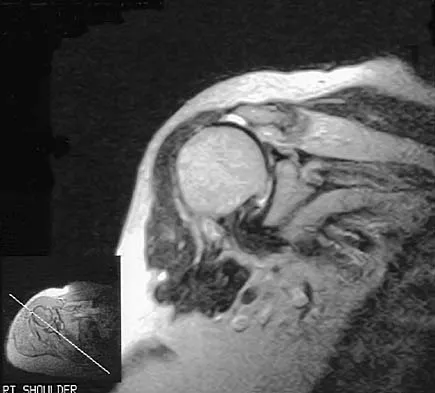

A 72-year-old woman who fell on her right shoulder while using a treadmill is now unable to elevate her right arm. An MRI scan is shown in Figure 7. What is the most likely diagnosis?

Explanation

The MRI scan reveals a large chronic rotator cuff tear with retraction and fatty infiltration atrophy of the supraspinatus and infraspinatus tendons. This tear is responsible for the patient's severe weakness and inability to elevate the arm.